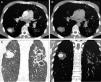

Cortes axiales de TC en ventana de mediastino: lesión en el LID, de bordes bien definidos, con captación de contraste en fase arterial (A superior) y lavado en fase venosa (B superior). Cortes coronales de TC en ventana de parénquima (A inferior) y en ventana de mediastino (B inferior) en fase arterial: lesión nodular captante en LID e imágenes de bronquiectasias y cavitaciones extensas en hemitórax izquierdo.

Varón de 33 años, rumano, que acudió al servicio de urgencias de nuestro hospital por cuadro de tos y hemoptisis. Refirió fiebre de 48horas y sudoración nocturna de 2 semanas de evolución. Como antecedente señaló una tuberculosis (TB) pulmonar tratada hacía 5 años. El paciente asociaba clínica de distrés respiratorio. Con estos datos se realizó una radiografía de tórax identificándose una opacidad alveolointersticial bilateral. Posteriormente se efectuó una tomografía multidetector (TCMD) torácica con contraste (CIV) que mostró varias consolidaciones, algunas cavitadas, bronquiectasias extensas y una lesión redondeada bien definida de 3cm en el segmento apical del lóbulo inferior derecho (LID) que presentaba, en fase arterial captación de contraste y en fase venosa lavado del mismo (fig. 1). Estos hallazgos se interpretaron como afectación tuberculosa con una imagen de probable seudoaneurisma de Rasmussen.